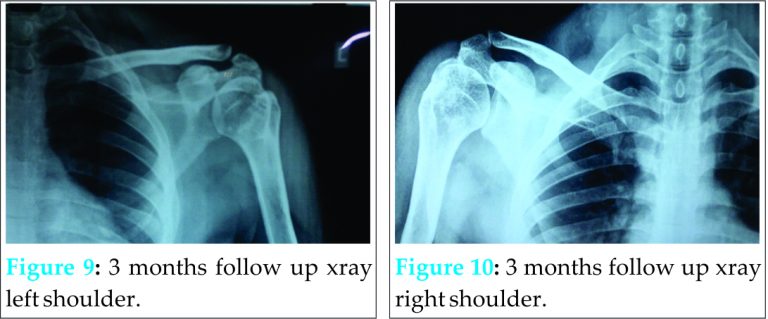

At the end of 3 months, the side reduced closed had full abduction, no complaints of pain and the side reduced open had 150-160 degrees range of motion (Fig. 6, 7, 8) with 3 month follow up X-ray also posted showing union of greater tuberosity (Figs. 9, 10).